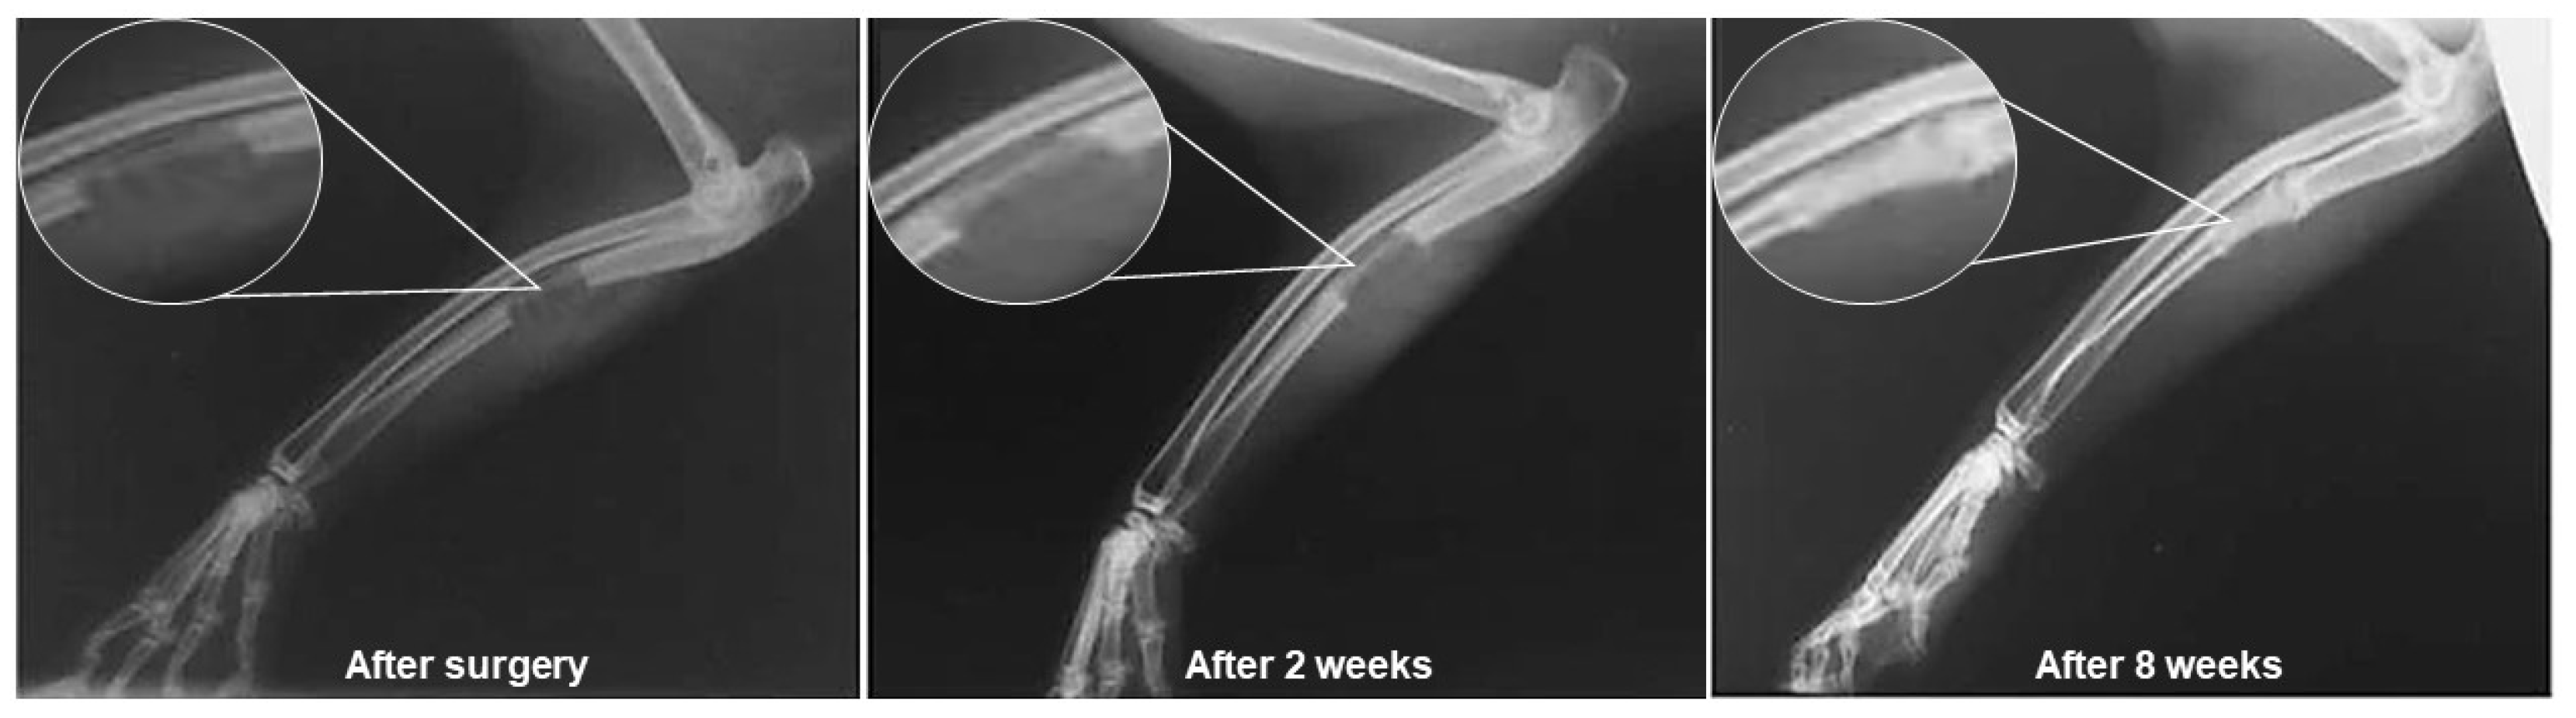

- Hafezi, F.; Hosseinnejad, F.; Fooladi, A.A.I.; Mohit Mafi, S.; Amiri, A.; Nourani, M.R. Transplantation of nano-bioglass/gelatin scaffold in a non-autogenous setting for bone regeneration in a rabbit ulna. J. Mater. Sci. Mater. Med. 2012, 23, 2783–2792. [Google Scholar] [CrossRef]

| Gelatin-chitosan/ BG 58SiO2–40CaO–5P2O5 | Scaffolds | Lyophilization | Increase of ~80% in the amount of new bone tissue formed after 8 weeks of implantation | [200] |